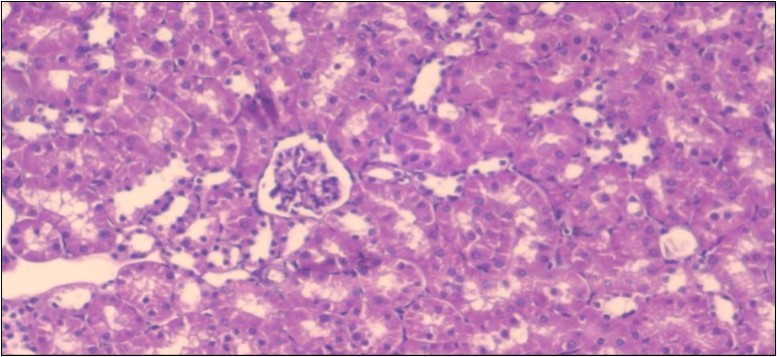

The histological examination of the kidney of the control rats fed on a standard diet showing normal rounded capsules with normal Bowman's glomeruli, round proximal tubules and elongated distal tubules with high cuboidal cells figure 1. The rats fed (HFD) showed fatty degeneration of the tubules with eosinophilic material deposition, glomerular atrophy with wide urinary space and distal tubules with extrusion of nuclei into lumen figure 2. By comparison kidneys of rats which were treated by fennel after being obese and the control rats observed partial improvement in both Bowman's capsules and proximal tubules. Note the distal tubules show less focal fatty infiltration figure 3.While examination of rats kidney that were treated by ator after obesity showed improvement in Bowman's capsules with normal glomerular and partial improvement in proximal tubules and distal tubules, figure 4. Kidney of rats that were treated by fennel and ator after obesity and the control rats showed high improvement in the tissues with normal glomerular and that Most of Bowman's capsules and renal tubules, restoring their normal appearance figure 5.

Figure 3.Photomicrogragh of kidney section of treated rat with fennel herb showing partial improvement in both Bowman's capsules and proximal tubules. Note the distal tubules show less focal fatty infiltration, (H&E) (40X)

Figure 4.Photomicrogragh of kidney section of treated rat with Ator drug showing improvement in Bowman's capsules with normal glomerular and partial improvement in proximal tubules and distal tubules, (H&E) (40X).